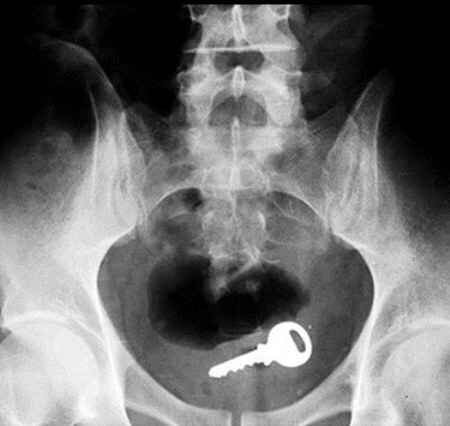

Одним из лидеров недели в Twitter стал хештег #WeirdThingsToPutUpYourAss (Странные штуки, которые суют в задницу). Проктологи со всего мира поделились рентгеновскими снимками содержимого анусов своих пациентов. Выяснилось, что огурец - еще не самое удивительно, что можно обнаружить там, где не светит солнце.